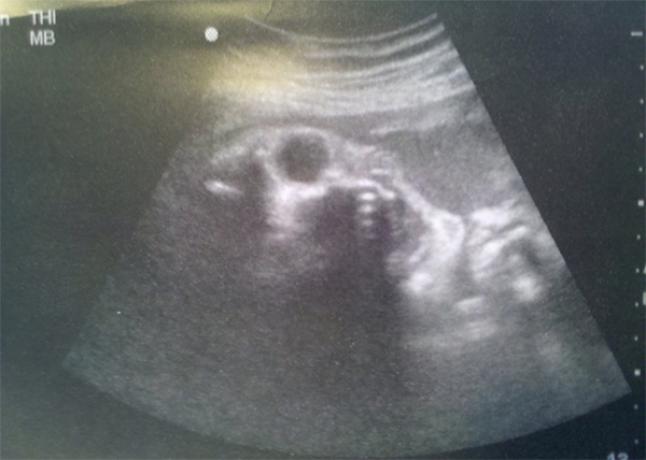

Tak si už poďme konečne povedať, prečo že to ľuďom tak jebe. Je to jednoduché. Za všetko zlo na svete (a teda aj jebnutosť) môže prenatálny ultrazvuk, aspoň teda podľa vnimavehotehotenstva.sk. Asi ste doteraz netušili, že každá vaša bunka obsahuje svätyňu živej hmoty - vlnový genóm. A že DNA dokáže vydávať rôzne zvuky. Ja to už teraz viem, a tak sa už nenechám oklamať svojimi nedokonalými zmyslami a keď najbližšie budem mať pocit, že ma o tretej ráno zobudila intelektuálna debata miestnych lovcov a zberačov pod našimi oknami, budem vedieť, že to len DNA z mojich mŕtvych kožných buniek nadáva, že som si zas zobral celú perinu pre seba. No a ultrazvuk úplne potlačuje rôznorodosť verbálneho prejavu DNA a tá už vydáva len jeden tón. „Ultrazvuk ublížil molekulám DNA a ony si to zapamätali. Molekuly DNA zažili silný šok, po ktorom sa dlho spamätávali a nakoniec vytvorili vlnový fantóm bolesti a strachu, ktorý zostal na mieste pre nich strašného experimentu. Pod vplyvom tohto fantómu aj druhé, nové molekuly DNA prežili podobný šok, ktorý na nich zanechal rovnaké následky.“ Slovami vnimavejtehotnej, je to akoby ste počítaču zadávali rôzne úlohy a na všetky dostávali rovnakú odpoveď. Slovami mojimi, ako by ste sa rozprávali s konšpirátorom. Na toto všetko prišli ruskí vedci, ktorí síce nie sú vedci a všetci sa im posmievajú, ale veď vieme, že farmaloby sa nezastaví pred ničím. Títo vedci vždy odmietali robiť pokusy s ľudskou DNA, ale škody už boli napáchané a obnoviť genofond ľudstva nebude jednoduché. Ak by som veril, že DNA vydáva zvuky, tak by som si aj ja kurva rozmyslel, či s ňou budem robiť pokusy. Predstavte si DNA identifikáciu magora, čo znásilní a zabije dieťa. Určite by som to déenáčko nemal chuť počúvať. Páni vedci samozrejme zabudli (alebo nemali čo zabudnúť), že množstvo život zachraňujúcich terapií, vrátane inzulínovej, je možných len vďaka produkcii ľudských proteínov v baktériách a kvasinkách. Samozrejme po tom, čo sa do nich vloží kus ponížením kričiacej ľudskej DNA, obklopenej fantómom bolesti a strachu.

Ultrazvuk môže za autizmus (už to nie je očkovanie) a vrodené chyby. Predstavujem si to tak, že podľa toho, koľkokrát bola matka na ultrazvuku, od toho sa bude odvíjať stupeň poškodenia. Takže pozor, nemusí sa narodiť práve Rain Man. Pokojne to môže byť sebecký hajzel, parkujúci cez dve miesta pre vozíčkarov. Poviete si, že je jebnutý. Nie je. Alebo asi je, ale nemôže za to. Jeho DNA jednoducho piští v jednom tóne, fantóm strachu a bolesti sa vznáša nad jeho vlnovým genómom. A to všetko preto, že jeho manka chcela vedieť, či mu má kúpiť ružové alebo modré dupačky. Našťastie nám vnimavatehotna.sk povie, ako sa proti tomu brániť. Nechoďte na ultrazvuk. Ona pri svojom prvom dieťati bola dvakrát a bohužiaľ to už späť nedá. Pri druhom bola raz na päť sekúnd mesiac pred narodením, a hneď išla radšej objímať päťstoročné duby. A všetko je OK, lebo u nej to vyšlo. Takže milé dailymatky, ak vaše deti neposlúchajú, myslia len na seba, pozorujete u nich sklony k agresivite a znížený intelekt a ich DNA len zúfalo piští jedným tónom namiesto vyhrávania Svätenia jari, môžete si za to samy. Polihovať pod ultrazvukom, na to by vás bolo, ale lesy sú plné nikdy neobjatých stromov.